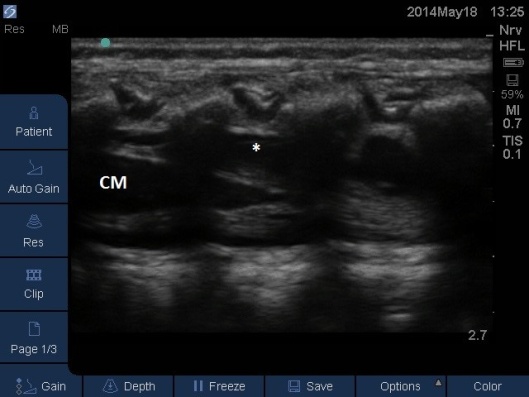

- The LA spread can be monitored to ensure it has spread high enough for the intended surgery. See Fig 11,12 and Video

- In neonates the probe can stay in the midline sagittal position, in older children it will be necessary to use the paramedian sagittal views (left and right) as the echo windows are greatest between the laminae. The probe moves synchronously cephalad as the LA spreads higher.

Fig 11. Ultrasound Probe in Midline Longitudinal position over the lumbar spine. White * indicates local anaesthetic seen as anechoic area in posterior epidural space. CM = conus medullaris (anechoic with hyperechoic outline) with hyperechoic linear pattern of cauda equine attached.